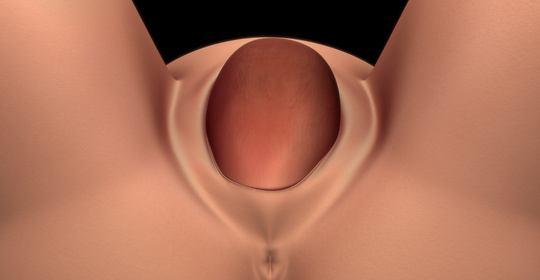

枕橫位入盆:孕期小知識,詳細瞭解及時處理!

胎膜破裂:孕期預警信號,科普處理措施與防範方法!

胎盤滯留宮腔:產後康復小知識,瞭解症狀及處理!